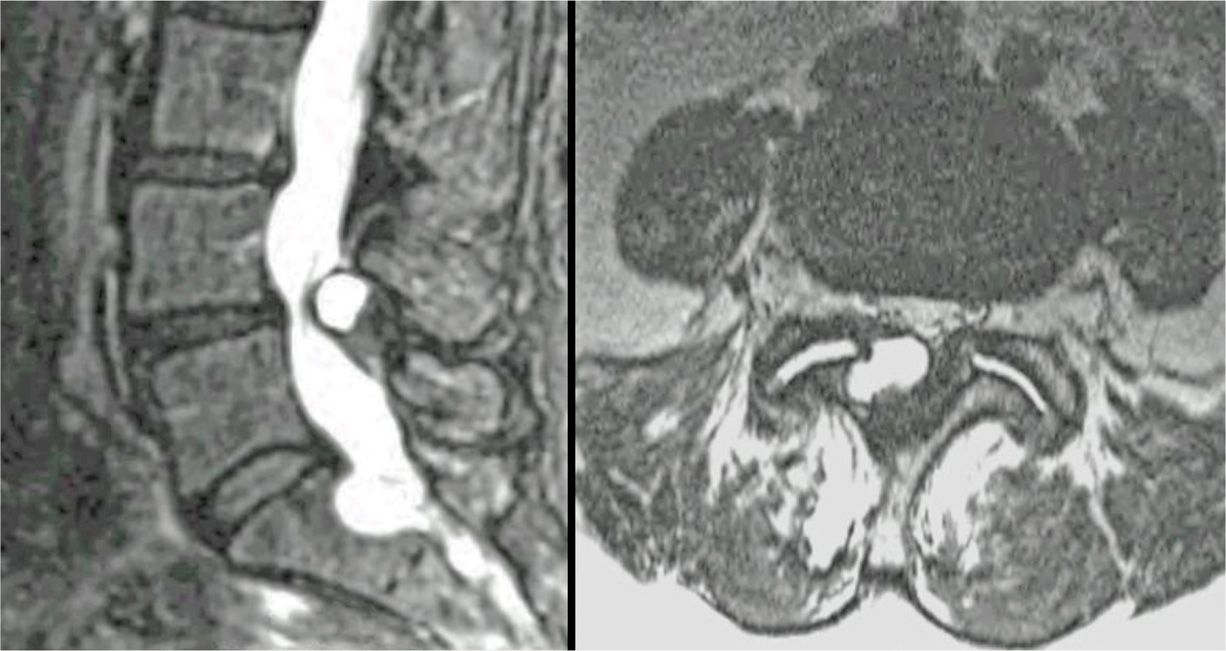

Lumbar facet joint synovial cyst Dr Matty Wong Chiropractor Facet Joint Fluid Mri the lumbar spine mri demonstrating normal curvature and facet joint fluid is considered a reliable sign of. we investigated whether facet joint effusion on conventional supine mri indicated increased abnormal motion in. facet joint degeneration, degenerative disc disease and fluid in the facet joints can be readily detected by. radiologists must also be aware of facet. Facet Joint Fluid Mri.